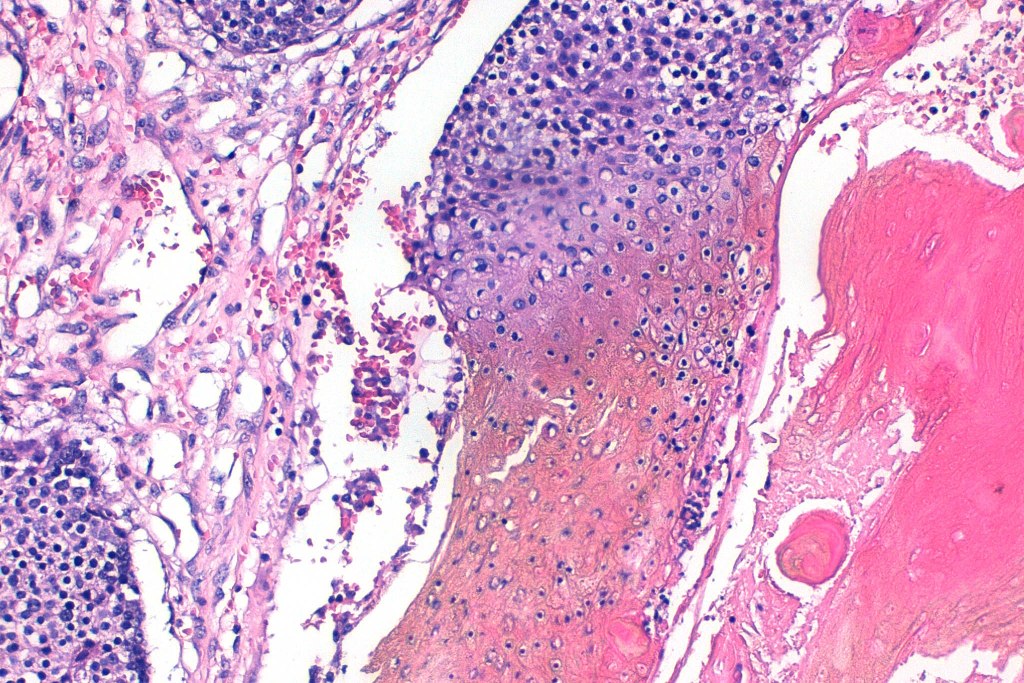

•Multilobulated tumor in dermis +/- subcutaneous fat with a fibrous pseudocapsule

•Basophilic small cells which transition towards supramatricial (orange staining) and ultimately ghost cells with intensely eosinophilic cytoplasm

•Late features include calcification and bone formation

•Foreign body reaction